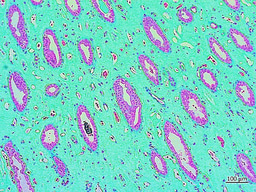

We analyzed clinical cohorts of patient renal papillae tissues obtained via nephrectomy (n = 34) from the UCSF Medical Center and the Department of Urology alongside patient pathology data reports. These data were categorized as stone-formers (SF) vs. non-stone formers (NSF) to examine the histopathology and genetic (bulk RNA-sequencing) composition of patient samples in the two groups. Cross-sections of the renal papillary tip were sectioned, mounted, and stained at the Zuckerberg San Francisco General Hospital and Trauma Center, to primarily assess the biomarkers of renal calcification via histology with Alizarin Red dye, collagen deposition with Masson’s Trichrome dye, and epithelial-mesenchymal transitions/fibrosis with the immunohistochemistry Vimentin-DAB antibody. These biomarkers occur at the papillary tip region, as precursors of renal fibrosis, epithelial dysfunction, and cell death prior to calcification.

For histopathology and immunohistochemistry classifications, we delineated the stone former vs. non stone former samples into a total of 19 patient cohorts with biopsies of the renal papillary tip region, of which 8 patient samples were categorized as non-stone formers, and 11 patient samples were categorized as stone-formers. The none stone-formers were clinical subjects exhibiting diseases other than renal calcification, including renal carcinoma. We conducted digital pathology multiplexing analyses via quantitative pathology software (quPath GitHub) and trained an artificial neural network (ANN) to quantify biomarkers of interest pertaining to renal calcification and kidney injury, across the cortex-to-tip region of the renal papillae among stone former vs. non-stone formers.

To facilitate ANN-assisted quantification, we trained the algorithm to segment and identify the renal papillary tip region within four specific areas assigned to tissues ranging from the cortex-to-tip region, and labelled these areas the ‘cortex area,’ Z2 (zone two) area, Z3 (zone three) area, and Z4 (Zone 4) area, respectively (Figure 3). Each region assigned within the medullary-papillae region maintained specific morphological features of tissue pathology [Ho 2018], including myoglobin renal casts, inflammatory markers of reactive nuclear changes, amyloid deposition, epithelial thinning with a beaded, ropey appearance, and intratubular eosinophilic pigmented casts that were observed in our study.  A few renal stone forming patients demonstrated sediments of glomerular amyloidosis, including features of glomerular amyloid balls to indicate advanced amyloidosis in renal pathology. While the glomeruli of non-stone formers indicated normal morphology, or minimal amyloid deposition with nearly normal glomeruli (Figure 3).

Figure 3: Histopathology data with stone formers vs. non-stone formers, the top image shows the method of zone classification used to train an artificial neural network with quPath software to quantify regions of interest (Z1-Z4) in the renal papillae. The tissue sections were stained with H&E to view inflammatory biomarkers in stone formers, including renal casts and epithelial thinning with a ropey or beaded appearance. In renal papillary sections of stone formers, the trichrome dyes indicated a higher percentage of green for increased collagen deposits, Alizarin red stained a higher percentage of crimson for calcium deposits, and vimentin DAB stained a higher percentage of brown to represent epithelial mesenchymal transitions during renal nephrolithiasis and glomerular amyloid balls in stone formers [Jeewandara 2023].

Not all cross-sections of the renal papillary tip maintained all the features of interest i.e. the cortex area to Z2-to-Z4 across the cortex-to-tip region, and as such the ANN was trained to classify the tissue sections accordingly (Figure 3). Using GraphPad Prism software, the initial measurements of digital pathology were analyzed to identify significantly higher levels of renal calcium deposits, seen as crimson aggregates (p value = 0.0017), collagen deposits that take up green colour (p value = 0.001), fibrosis that appear brown (p value = 0.0385), renal casts and inflammatory reactive nuclear changes seen with H&E images among stone former vs. non-stone former cohorts, quantified from the cortex-to-tip region of the renal papillae (Figure 4).